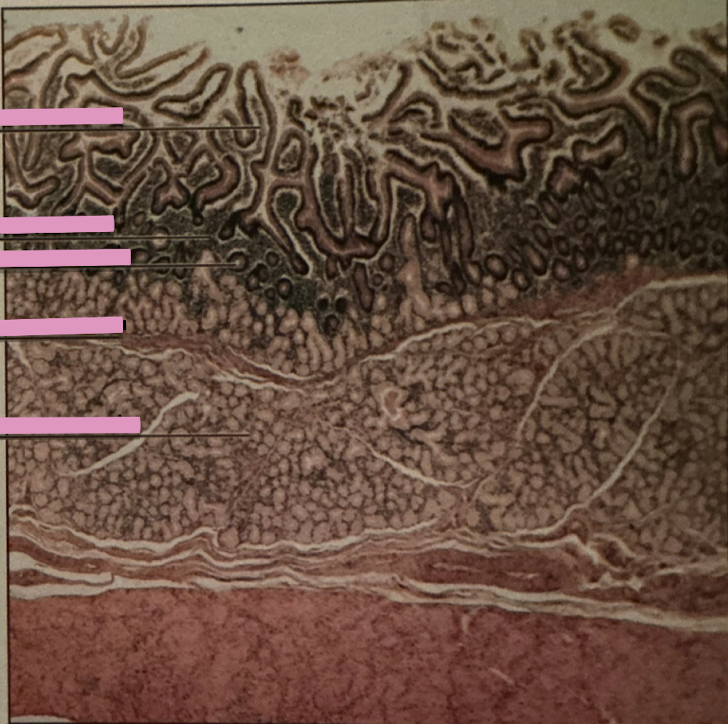

stomach at 40x

stomach at 100x

gastric pits

exocrine ducts from glands that lead to stomach lumen

gastric glands

exocrine epithelia secrete mucus, gastric acid, intrinsic factor, peptic cells, neuroendocrine cells, and stem cells

duodenum

brunner’s glands

intestinal epithelium

duodenum

________ receives chyme when stomach empties; exocrine release site for gallbladder & pancreatic secretions

intestinal glands

secrete mix of sucrase, maltase, & peptidases + definsins & enzymes

brunner’s glands

produce mucus-rich alkaline secretion to protect from acidic content, lubricate walls, & enable absorption

goblet cells

single-celled exocrine glands secrete mucus